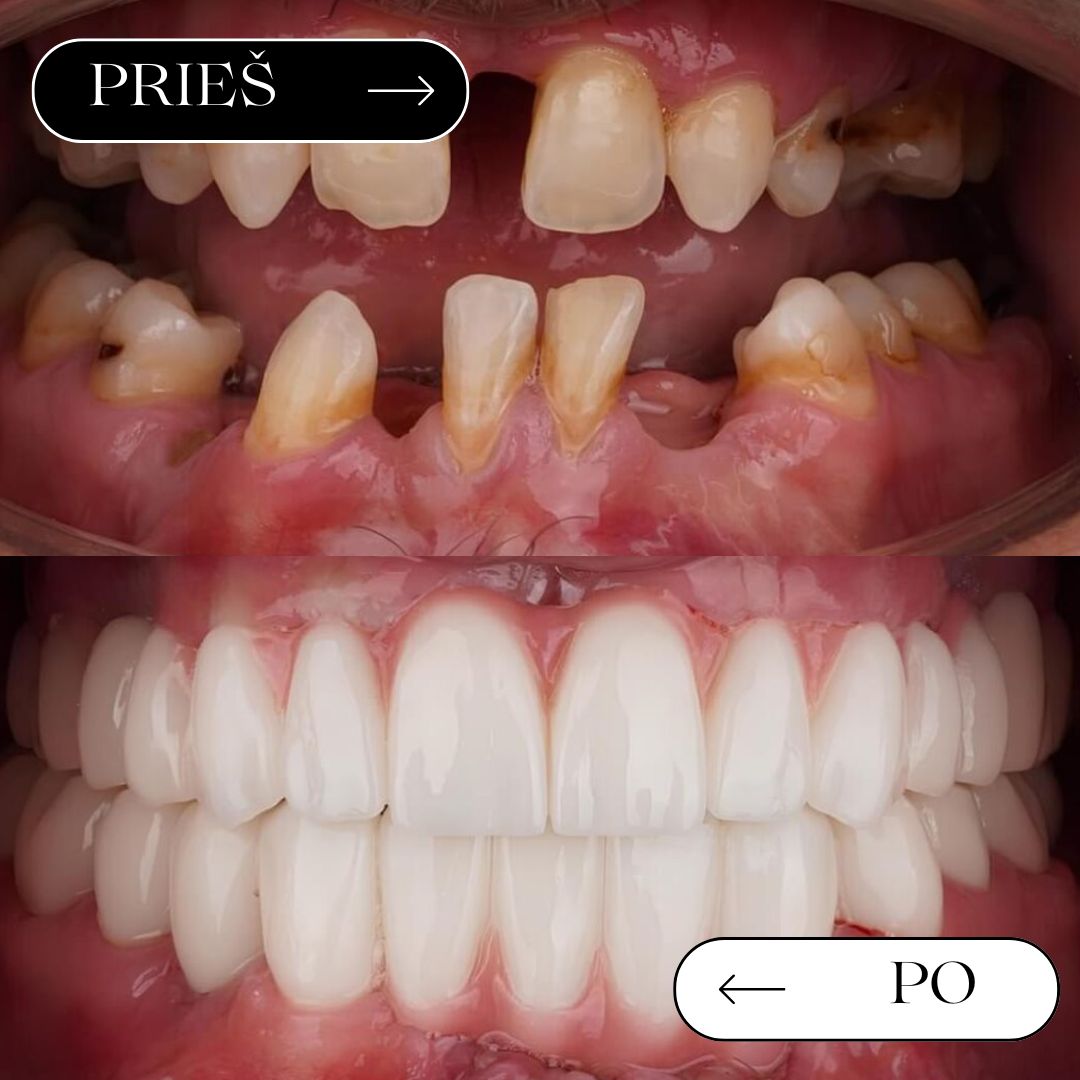

Prieš / po

rezultatai

Geriausias įrodymas – realūs pacientų pokyčiai. Atkurta estetika ir funkcija gali leisti vėl šypsotis be baimės.

Pilna viršutinio žandikaulio reabilitacija

Šypsenos reabilitacija Straumann implantais